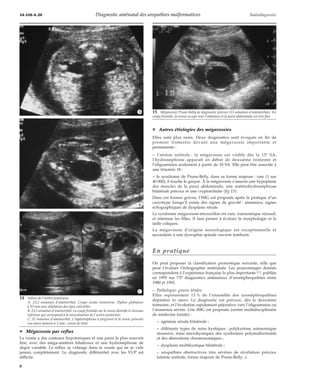

¦ Autres étiologies des mégavessies

Elles sont plus rares. Deux diagnostics sont évoqués en fin de

premier trimestre devant une mégavessie importante et

permanente :

– l’atrésie urétrale : la mégavessie est visible dès la 13e SA,

l’hydronéphrose apparaît en début de deuxième trimestre et

l’oligoamnios seulement à partir de 18 SA. Elle peut être associée à

une trisomie 18 ;

– le syndrome de Prune-Belly, dans sa forme majeure : rare (1 sur

40 000), il touche le garçon. À la mégavessie s’associe une hypoplasie

des muscles de la paroi abdominale, une urétérohydronéphrose

bilatérale précoce et une cryptorchidie (fig 15).

Dans ces formes graves, l’IMG est proposée après la pratique d’un

caryotype lorsqu’il existe des signes de gravité : anamnios, signes

échographiques de dysplasie rénale.